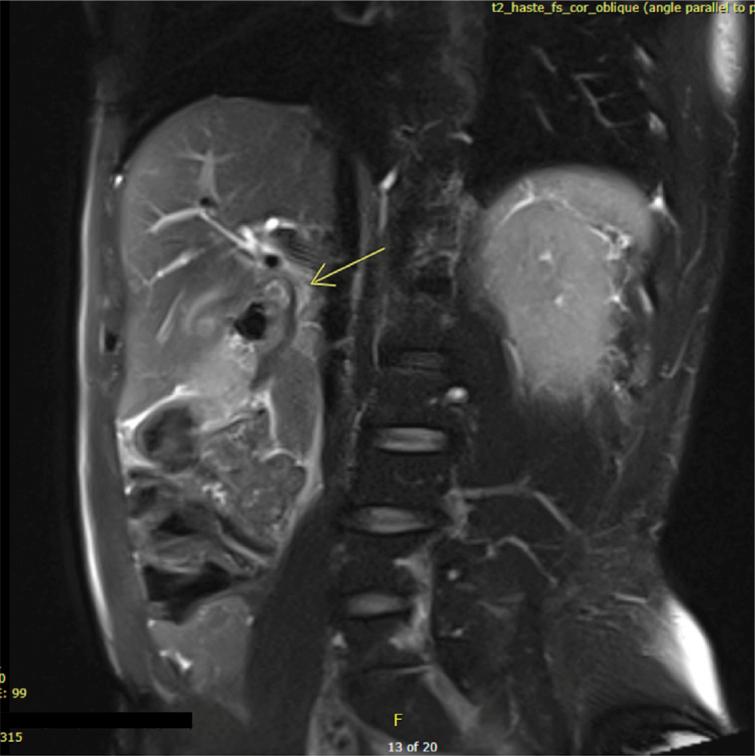

CASE REPORT

This is an unusual case of a 54-year-old male who presented with acute cholecystitis complicated by haemobilia and Mirizzi-like obstruction, in the setting of cystic artery pseudoaneurysm rupture. Initially, urgent transcatheter angiographic embolization of the cystic artery was performed to achieve hemodynamic stability. However, a triphasic computed tomography (CT) scan revealed the first attempt was unsuccessful, necessitating a second embolization. Subsequent imaging confirmed satisfactory embolization; however, a small area of liver necrosis was observed adjacent to the gallbladder. The patient was stable at discharge from the hospital and had an uncomplicated interval cholecystectomy.

这是一例不同寻常的病例,一名54岁男性患者,表现为急性胆囊炎并发胆道出血和Mirizzi样梗阻,同时存在胆囊动脉假性动脉瘤破裂。最初,对胆囊动脉进行了紧急经导管血管造影栓塞术以实现血流动力学稳定。然而,三相计算机断层扫描(CT)显示首次尝试未成功,需要进行第二次栓塞。随后的影像学检查证实栓塞效果满意;然而,在胆囊附近观察到一小片肝坏死区域。患者出院时情况稳定,并顺利进行了择期胆囊切除术。